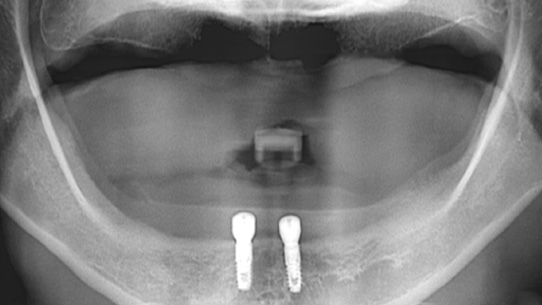

틀니가 번번히 탈락되어 일상생활이 불편하셔서 내원, 고정력이 없는 틀니를 사용하여 잇몸 염증과 통증 있으셨습니다. 상악의 경우

틀니를 오랫동안 착용하여 잇몸 뼈 소실이 심해 일반 틀니를 제작하고, 하악의 경우 임플란트 2개를 식립 후 임플란트 틀니를 제작해 드렸습니다.

상악은 잇몸뼈의 손실이 심한 상태

하악에 임플란트 2개 식립